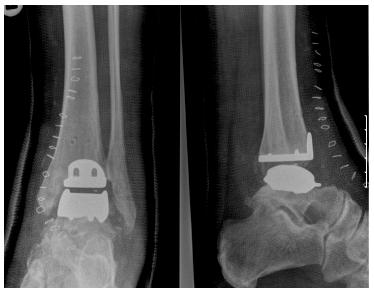

Total ankle replacement removes and then replaces both sides of the ankle joint with specially designed components, called prostheses. The tibial prosthesis consists of a polyethylene (medical grade plastic) and titanium base plate tray that is inserted into the tibia and fibula, giving the implant a wide base for support.

- The metal parts of the new artificial joint are then attached to the cut bony surfaces. A special glue/bone cement may be used to hold them in place.

- A piece of plastic is inserted between the two metal parts.